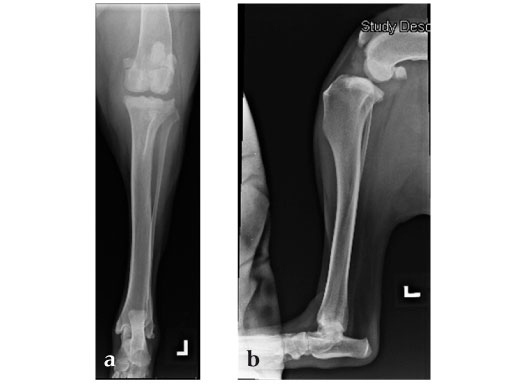

The stifle joint was surgically explored. All remaining remnants of the torn cranial cruciate ligament were debrided; in addition, the caudal pole of the medial meniscus was torn/crushed, and a partial meniscectomy of the damaged portion was performed. A TPLO plate 3.5 was applied to stabilize the fracture. The plate was applied in a neutral fashion. Postoperative x-rays revealed a tibial plateau angle of 5, and a correction of the torsion to 0 mm.

Follow-up x-rays at 8 weeks postoperatively revealed that the osteotomy had healed, and the dog was doing very well. The identical procedure was performed on the opposite stifle joint 2 months later. Healing was again obtained 8 weeks postoperative. Presently, the dog is about 1 year postoperatively and functioning very well.